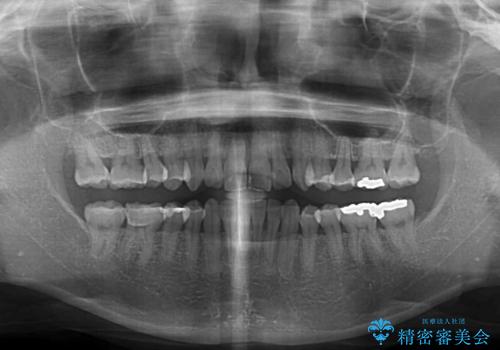

矯正治療の後戻り インビザライン・ライトによる矯正治療

- 40代女性

- 11ヶ月

- 矯正治療の後戻りを気にして来院された患者様です。

後戻りは軽微であったので、インビザライン・ライトにより矯正治療を行うこととしました。